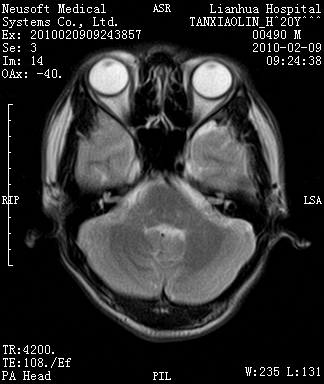

20岁男性患者,平时偶有头痛而无其他不适,现因持续头痛服药后无缓解而来院就诊。

松果体囊肿?

松果体区占位继发轻度脑积水?该患者有ct资料,我已发上。

考虑松果体囊肿。